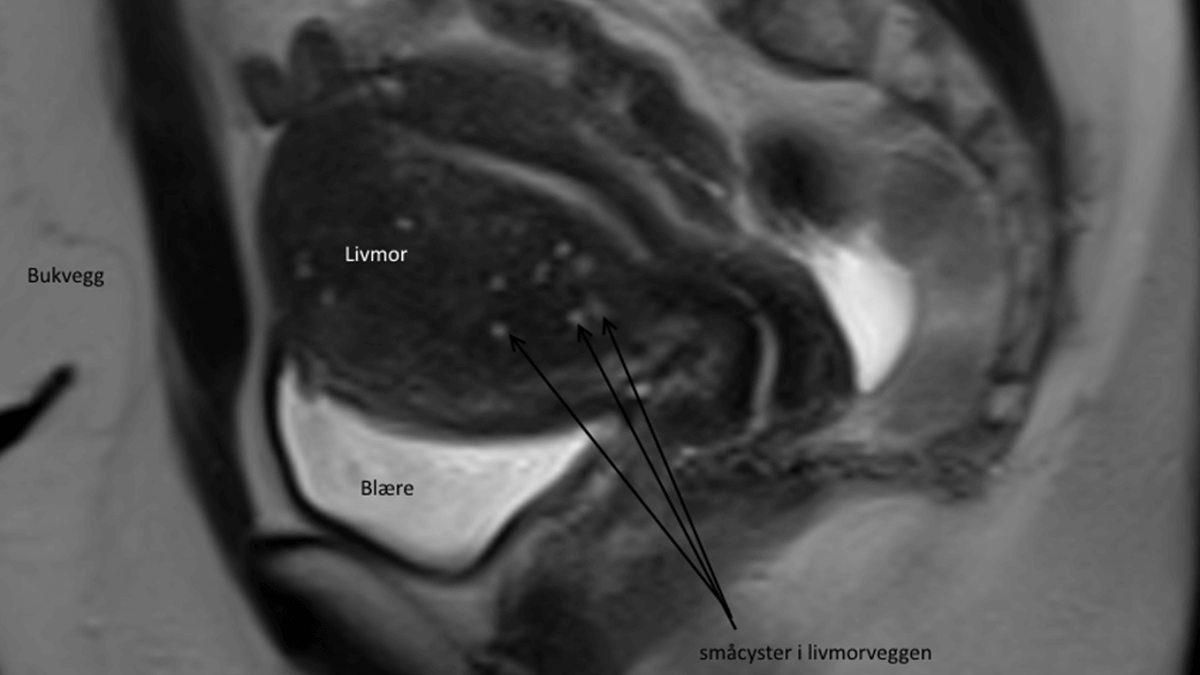

Ved en indvendig ultralydsundersøgelse (vaginal ultralyd) kan man opdage ca. 87% af alle tilfælde. Gynækologen mistænker adenomyose, hvis livmoderen er sfærisk/kugleformet, forstørret eller virker asymmetrisk og med vægge, som er forskellige af tykkelse. Nogle gange vil man kunne visualisere små blodfyldte cyster i muskelvæggen.